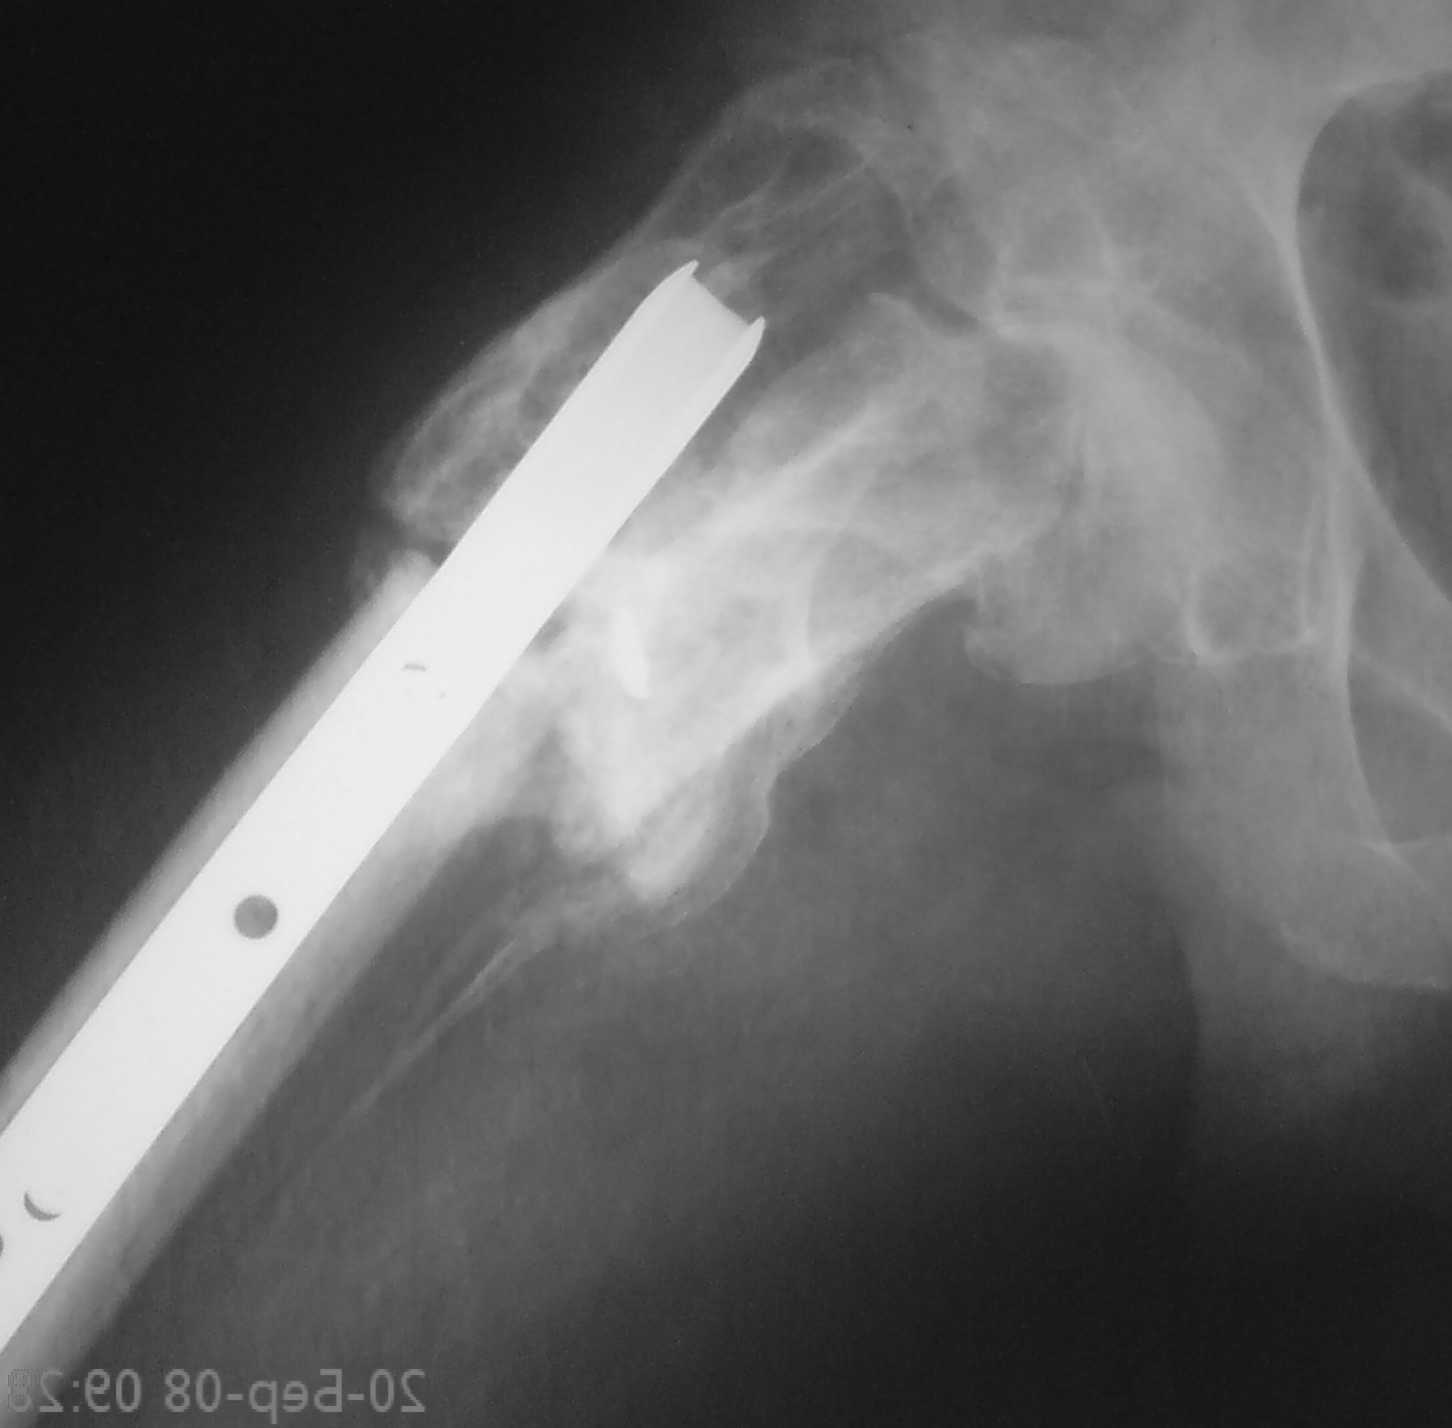

[Ortho] неправильно консолидированный перелом вертельной области (дополнение)

Имя     : DSC00410.JPG

Url     : http://weborto.net:8080/pipermail/ortho/attachments/20080325/cb38b33e/attachment-0003.jpeg